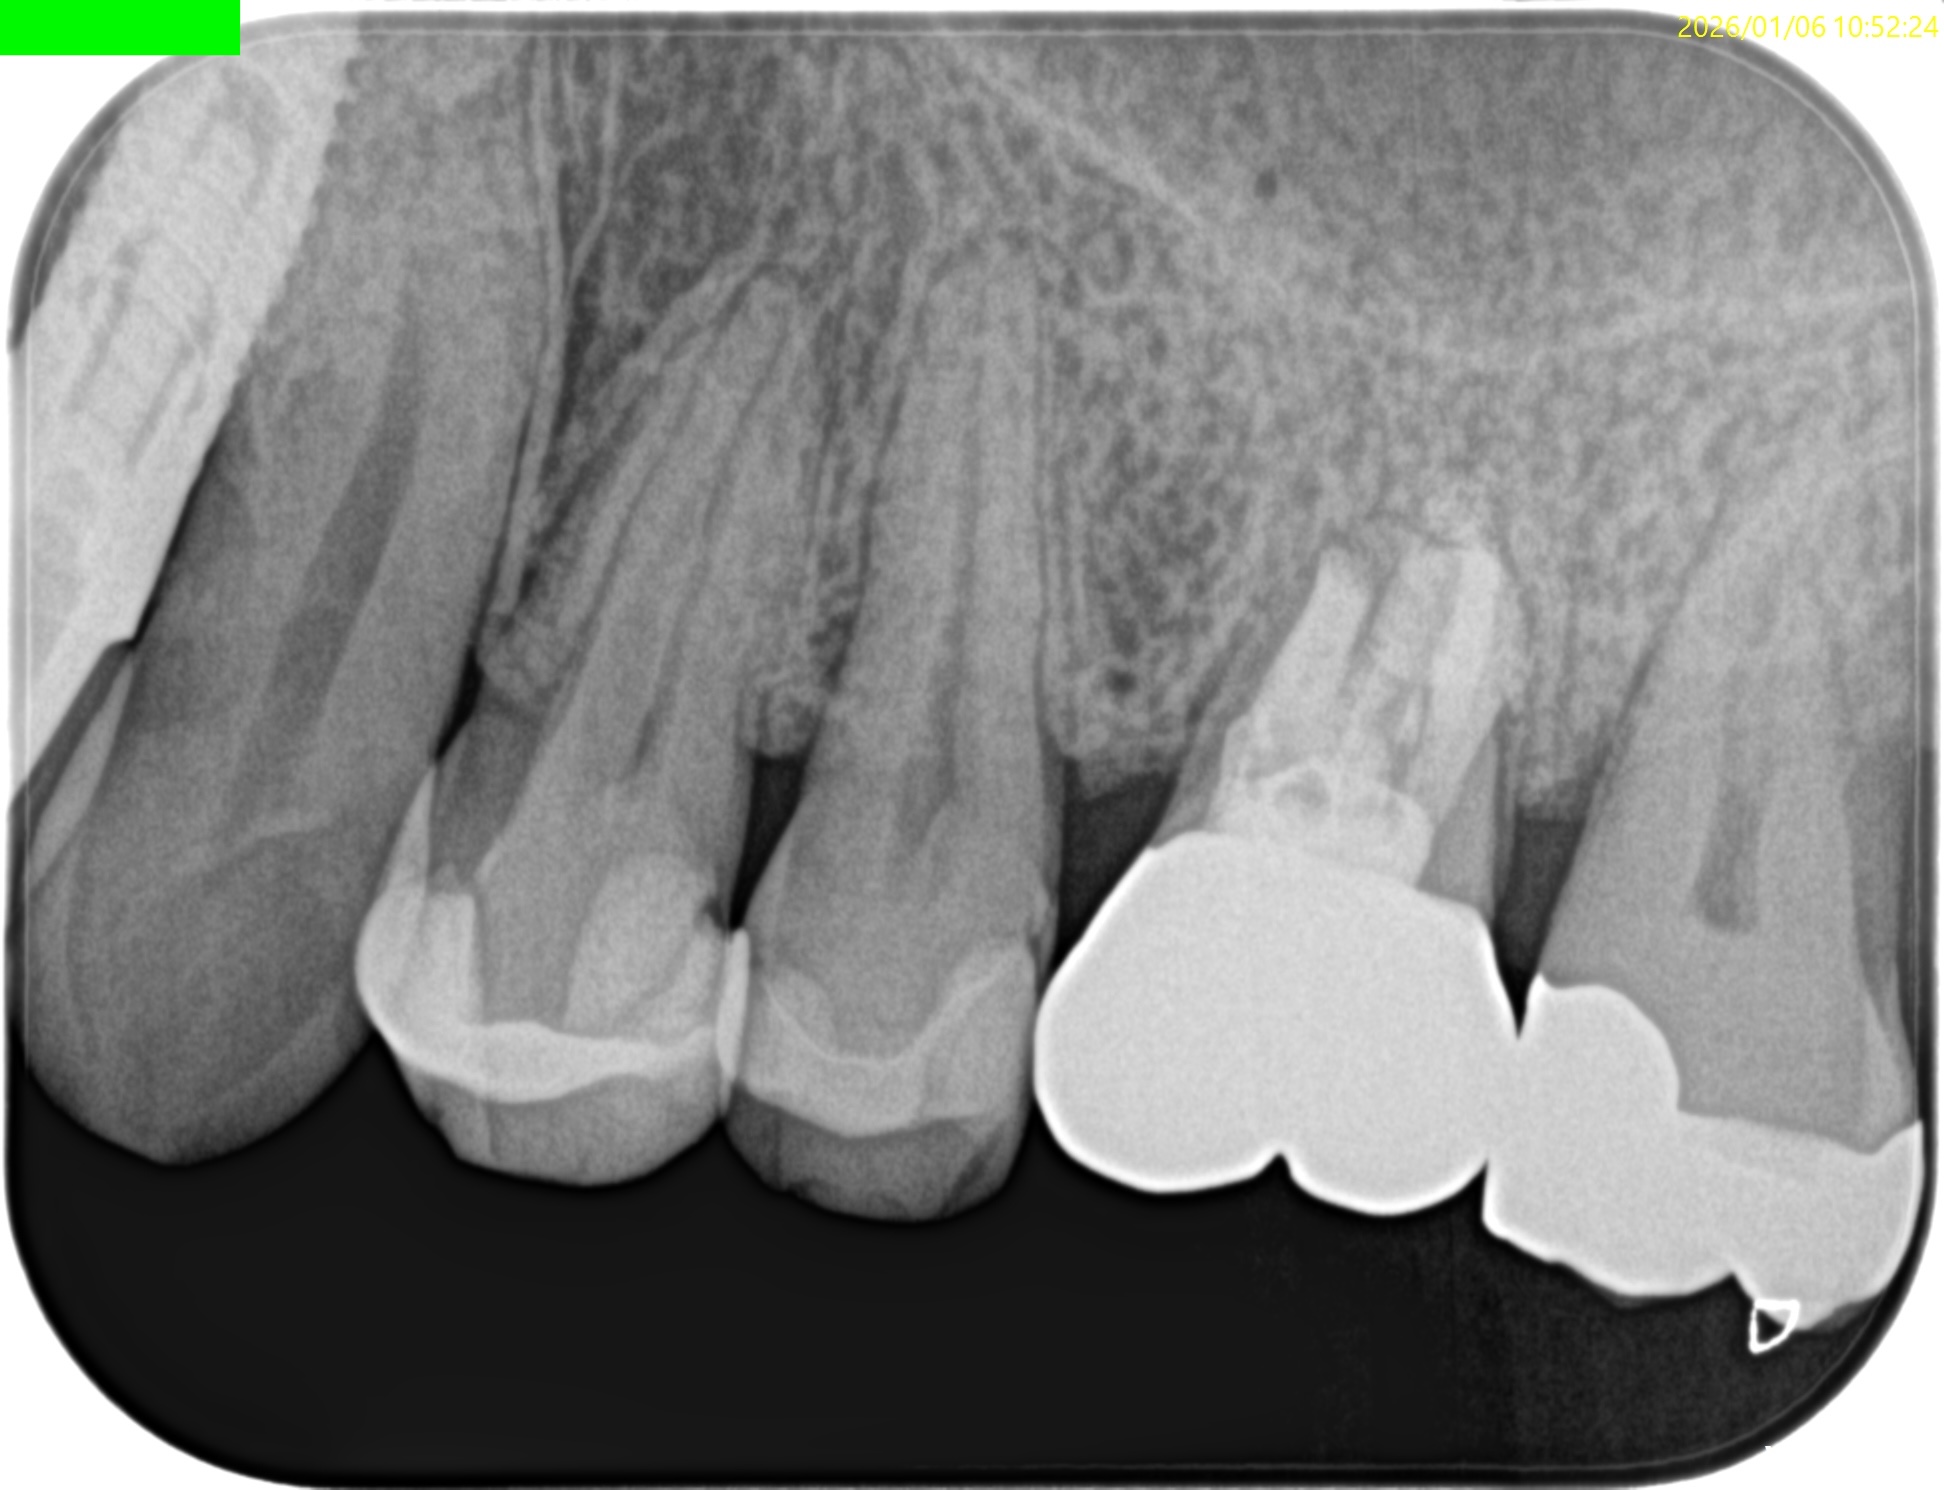

PA, CBCTも撮影した。

#14

MB

DB

P

初診時と比較した。

問題が劇的に解決していることがわかる。